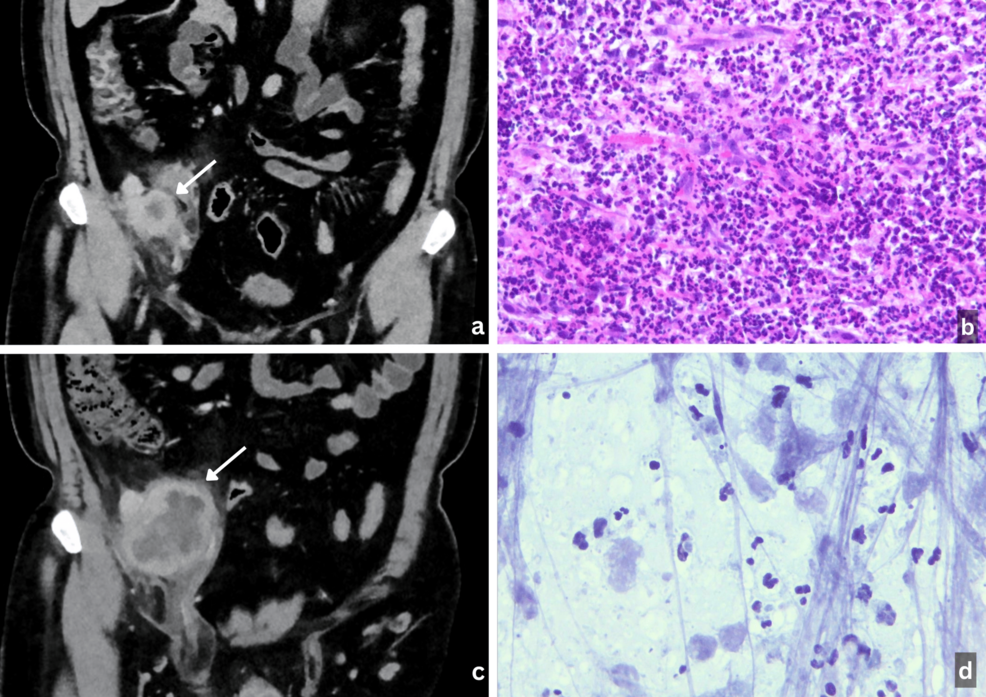

In one notable case, a 64-year-old woman with well-controlled HIV infection on antiretroviral therapy presented with a progressively enlarging, exophytic lesion on her scalp. Because of the patient’s HIV status and the appearance of the lesion, there was a strong clinical suspicion of Kaposi sarcoma. However, the initial punch biopsy proved inconclusive, illustrating a common hurdle in diagnosing these aggressive skin cancers.

When a lesion is deemed inoperable and clinical suspicion of KS is high, doctors may turn to empirical treatment. In the aforementioned case, the patient was treated with liposomal doxorubicin at a dose of 20 mg/m², which is the standard chemotherapy for Kaposi sarcoma.

The result was unexpected: after four cycles of treatment, the lesion showed marked clinical and radiologic regression. While liposomal doxorubicin has limited off-label activity against other cutaneous malignancies, its effectiveness in this case allowed the lesion to shrink enough for surgical intervention.

Subsequent surgical excision finally provided a definitive diagnosis: keratinizing squamous cell carcinoma. The surgery achieved tumor-free margins, and the patient remained recurrence-free at a six-month follow-up.